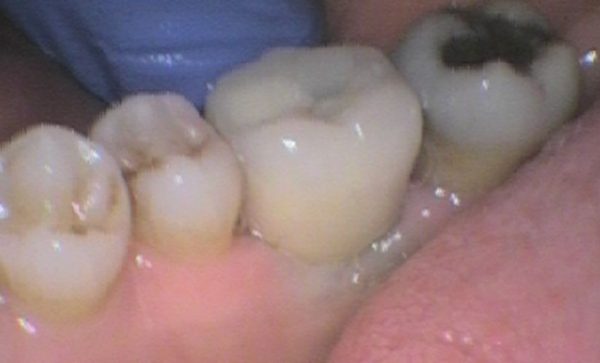

Case 12